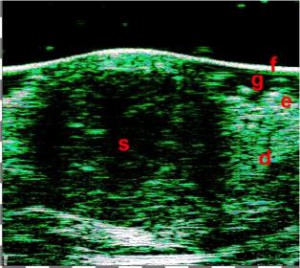

-Υπέρηχος Υψηλής Συχνότητας (HFUS) και Ιστολογία

-Έγχυση Πληρωτικών Υλικών (Fillers)